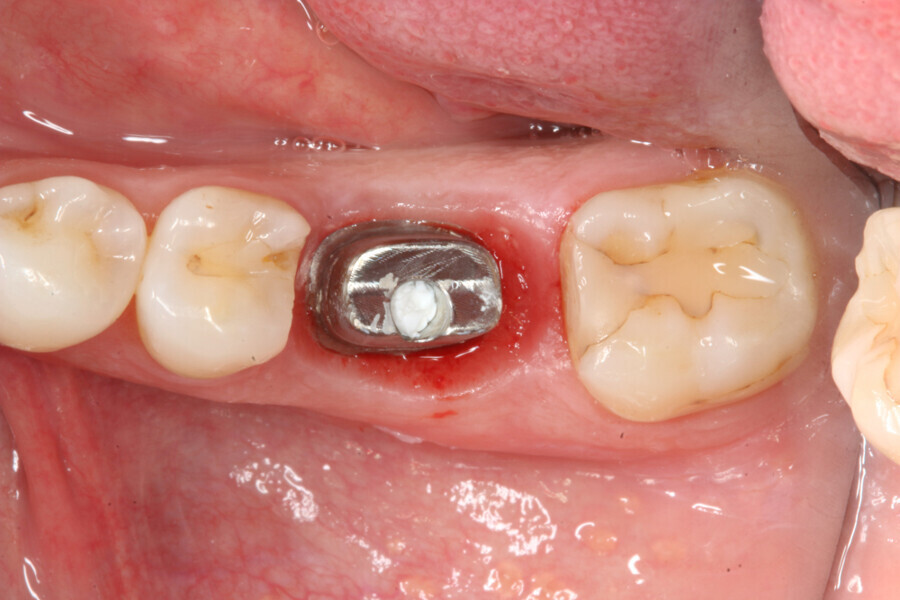

Immediately after implant placement (Fig. 5), the abutment position was registered with an intra-oral scan using Primescan (Dentsply Sirona; Fig. 6). At the end of the surgical procedure, the socket was grafted with Symbios (Dentsply Sirona) and a healing abutment was seated (Fig. 7). Radiographic evaluation was performed on the same day (Fig. 8). On basis of an intra-oral scan, an Atlantis abutment and Atlantis provisional crown were designed and fabricated with an Atlantis IO FLO (Fig. 9).

One week after implant surgery, healing was satisfactory and the abutment and provisional crown were inserted (Figs. 10–14).